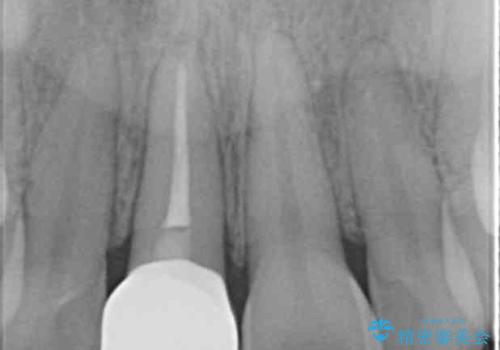

X線検査、歯髄(歯の神経)の検査を行ったところ、失活(歯の神経の死んだ状態)であると診断されました。

放置すると変色が進行するだけでなく、根尖病変も形成される恐れが強いことから、根管治療を行ったのちセラミッククラウンによる審美性の改善を計画します。